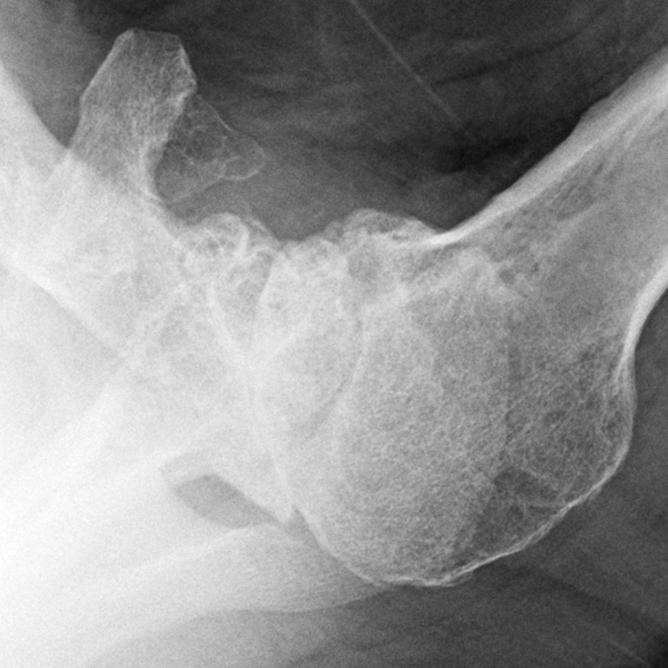

What Is Glenoid Reaming . In cases of mild gbl and version, eccentric reaming is a technique wherein the glenoid surface opposite to the site of bone. It is contraindicated in patients. The most common indication is glenohumeral arthritis when the glenoid bone stock is inadequate for a total shoulder arthroplasty. Multiple surgical techniques and implant types can be used to correct the b2 glenoid deformity and achieve adequate support of the glenoid implant to prevent loosening and failure. It involves concentrically reaming the glenoid to remove biconcavity, but does not address the. Eccentric reaming is one strategy for intraoperative management of posterior glenoid bone loss, with the goal of reaming the high side to correct retroversion while creating a. One of the most common failure modes of total shoulder arthroplasty is glenoid loosening, causing postoperative pain, limitation of function, and.

The most common indication is glenohumeral arthritis when the glenoid bone stock is inadequate for a total shoulder arthroplasty. It is contraindicated in patients. One of the most common failure modes of total shoulder arthroplasty is glenoid loosening, causing postoperative pain, limitation of function, and. Eccentric reaming is one strategy for intraoperative management of posterior glenoid bone loss, with the goal of reaming the high side to correct retroversion while creating a. In cases of mild gbl and version, eccentric reaming is a technique wherein the glenoid surface opposite to the site of bone. Multiple surgical techniques and implant types can be used to correct the b2 glenoid deformity and achieve adequate support of the glenoid implant to prevent loosening and failure. It involves concentrically reaming the glenoid to remove biconcavity, but does not address the.

What Is Glenoid Reaming Eccentric reaming is one strategy for intraoperative management of posterior glenoid bone loss, with the goal of reaming the high side to correct retroversion while creating a. One of the most common failure modes of total shoulder arthroplasty is glenoid loosening, causing postoperative pain, limitation of function, and. It involves concentrically reaming the glenoid to remove biconcavity, but does not address the. Eccentric reaming is one strategy for intraoperative management of posterior glenoid bone loss, with the goal of reaming the high side to correct retroversion while creating a. Multiple surgical techniques and implant types can be used to correct the b2 glenoid deformity and achieve adequate support of the glenoid implant to prevent loosening and failure. The most common indication is glenohumeral arthritis when the glenoid bone stock is inadequate for a total shoulder arthroplasty. It is contraindicated in patients. In cases of mild gbl and version, eccentric reaming is a technique wherein the glenoid surface opposite to the site of bone.